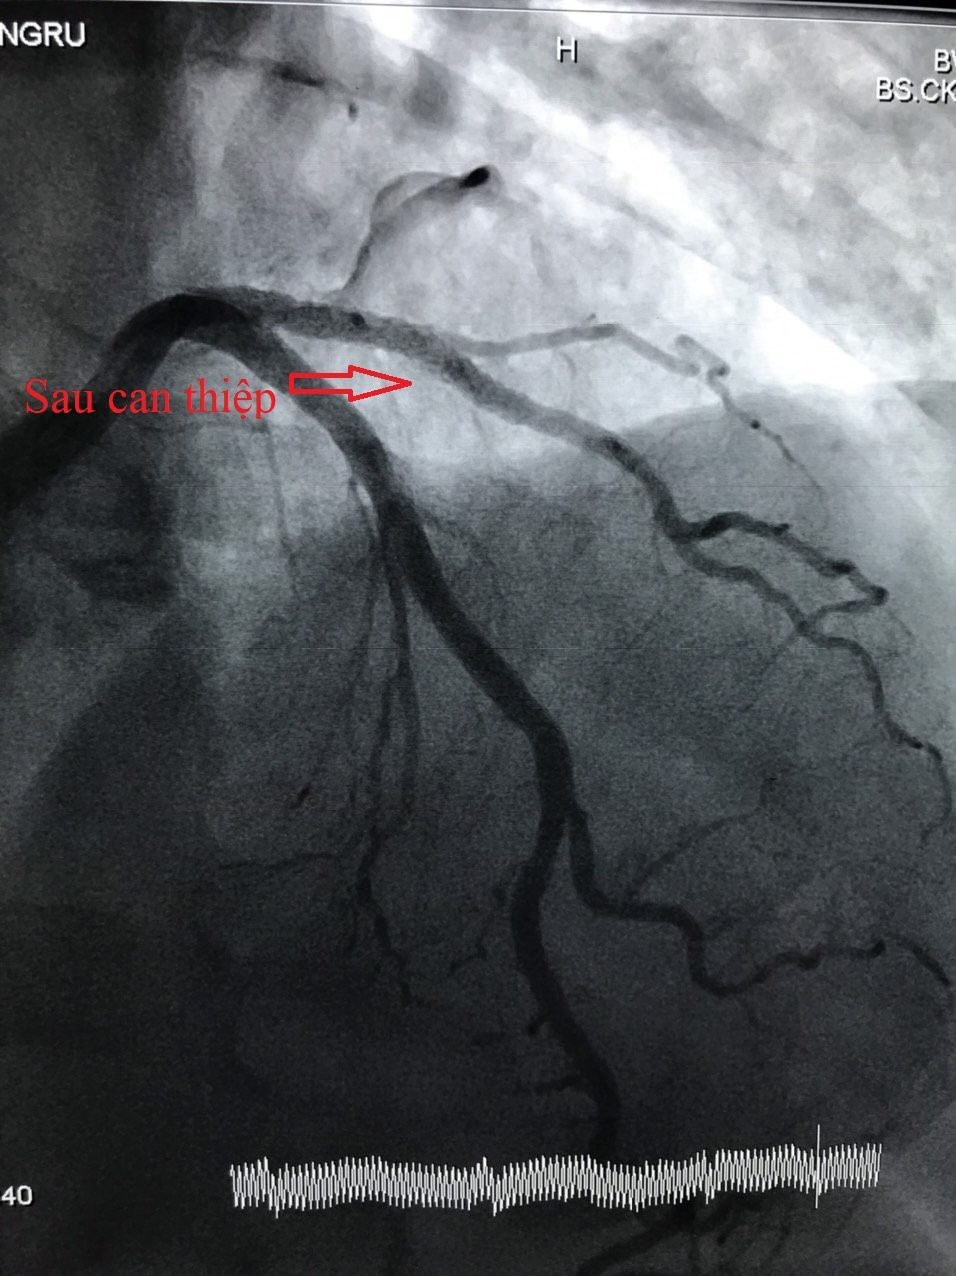

Qua khám và xét nghiệm xác định bệnh nhân W.Z., bị nhồi máu cơ tim cấp và có chỉ định can thiệp mạch vành cấp cứu. Kết quả chụp mạch vành ghi nhận động mạch liên thất trước (LAD) bị thâm nhiễm, hẹp 80% - 90% nhánh chéo 1. Ê-kíp các bác sĩ khoa Tim mạch can thiệp đã tiến hành can thiệp mạch vành cho bệnh nhân bằng cách nong bóng và đặt stent phủ thuốc với thời gian 30 phút do ThS.BS Trần Văn Triệu - Phó khoa Phụ trách khoa Tim mạch can thiệp và BS.CKI Nguyễn Văn Nhiệm thực hiện. Sau can thiệp, bệnh nhân tỉnh, mạch, huyết áp ổn định, giảm đau ngực nhiều và tiếp tục điều trị tại Khoa Tim mạch can thiệp.